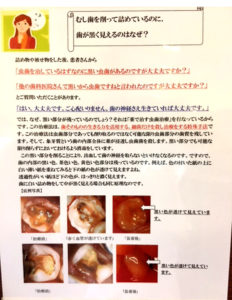

歯の神経を取ったはずなのに痛みが取れない場合は、4本目の歯の神経が見つかっていないのかもしれません

歯の神経を取ったはずなのに痛みが取れない。 治療は終了したと言われたが、どうしても痛みが取れない。 このようなことで吉本歯科医院に駆け込んで下さる患者さんがいらっしゃいます。 歯の神経の入口は 奥歯の場合 通常3つしかな […]

歯の神経治療は歯を失わないための基礎となる重要な治療

えば奥歯の神経(根っこ)の治療、保険治療では歯の神経(根っこ)は3本である、ほとんど3本であるということが、教科書に書かれております。 ですから、歯の根っこの治療(歯の神経治療)は3本までしか算定することができません。 […]